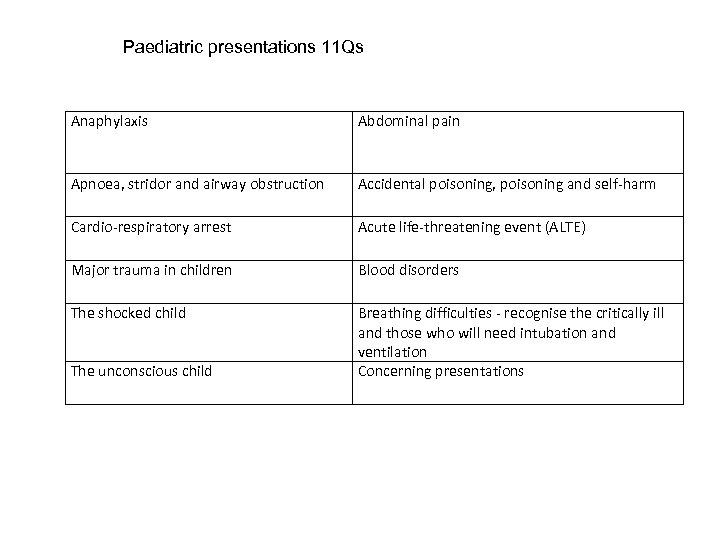

Paediatric presentations 11 Qs Anaphylaxis Abdominal pain Apnoea, stridor and airway obstruction Accidental poisoning, poisoning and self-harm Cardio-respiratory arrest Acute life-threatening event (ALTE) Major trauma in children Blood disorders The shocked child Breathing difficulties - recognise the critically ill and those who will need intubation and ventilation Concerning presentations The unconscious child